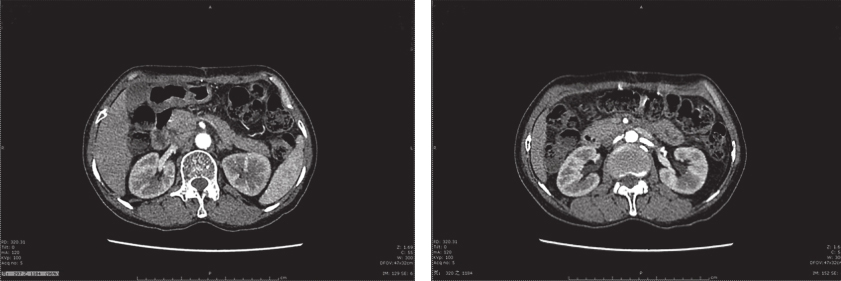

患者术后出现不全梗阻症状,经禁食、肠内营养等对症支持治疗,患者术后30天可完全经口进食,予以出院。出院后予以伊马替尼400mg/d治疗。截至目前,共随访15个月,未见肿瘤复发转移征象(图3)。

图3 术后1年腹部增强CT